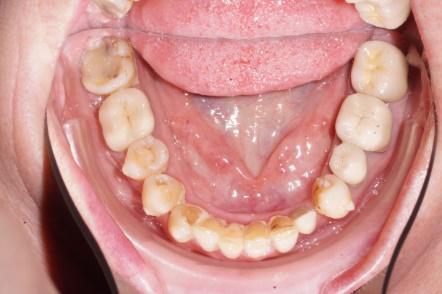

Un travail collaboratif

L’orthodontiste doit travailler en collaboration avec une équipe d’autres spécialistes pour définir un calendrier thérapeutique et donner au patient adulte le meilleur résultat.

- Intégrer la réalisation des prothèses et des implants

- Diagnostiquer les différents stades de la maladie parodontale (maladie de l’os et des gencives) et des facteurs de risque associés.